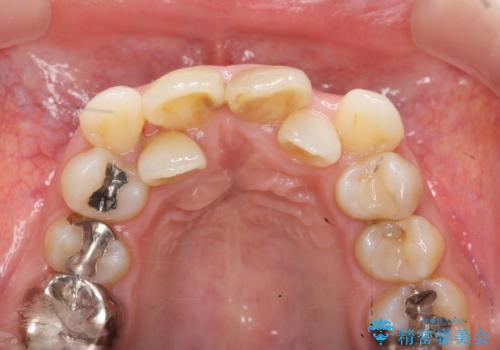

X線写真より不十分な根管治療、根尖病変、前歯の変色が認められます。

歯根の近接のみられる右上側切歯を抜去し、根管治療を伴うセラミック治療を計画します。

歯根近接について

叢生が著しく、歯根の近接が見られる場合歯磨きができず歯石がたまりやすく骨吸収の原因となることが多いです。

このような場合矯正や転位歯の抜去が治療方法として挙げられます。